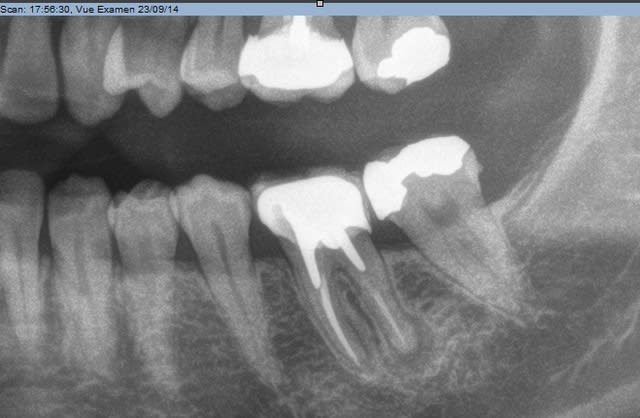

Je me permet de vous demander un conseil; suite à la découverte d'une image sur une 36 je me suis lancé dans la dépose et le retraitement, sauf que je ne progresse absolument pas... J'utilise les protapers de retraitement et rien ne se passe, malgré tous les solvants essayés : essence d'orange, eucalyptus ou rockle's (acétate de dexaméthasone).

Quelles sont les solutions restantes ? amputation, implant ?

La patiente m'a juste dit que ça précédente dentiste a passé plus de 15 heures sur cette dent, il y a 5/6 ans...

Par contre, le canal est surement ovale ou plat ce qui expliquerait la pêche à cause d'une zone non obturée.

Peut-être aussi un autre canal d'où l'intérêt des aides optiques.

Edit: en fait je pencherai plutôt pour un delta apical qu'on devine sur la radio.